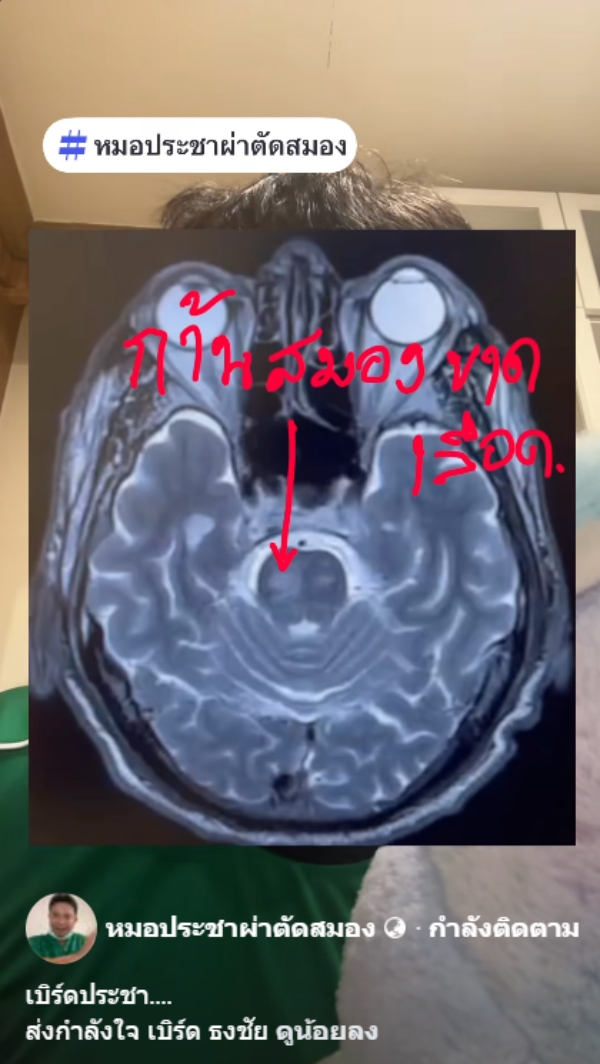

วันที่ 21 มกราคม 2569 เฟซบุ๊ก หมอประชาผ่าตัดสมอง โดย นพ.ประชา กัญญาประสิทธิ์ ประสาทศัลยแพทย์ โพสต์คลิปให้ความรู้เกี่ยวกับโรคสโตรก พร้อมข้อความ "เบิร์ดประชา....ส่งกำลังใจ เบิร์ด ธงไชย" พร้อมเผยว่า..

ขอให้ดูคลิป เบิร์ด ธงไชย เป็นตัวอย่าง โดยการพูดไม่ชัดเป็นอาการของก้านสมองขาดเลือด หรือสโตรก (STROKE) รวมถึงโรคอื่น ๆ ก็ได้ที่ทำให้สมองขาดเลือด ซึ่งถ้าไม่เป็นก็ถือว่าเป็นเรื่องที่ดี แต่หากเป็นก็ขอให้หายไว ๆ